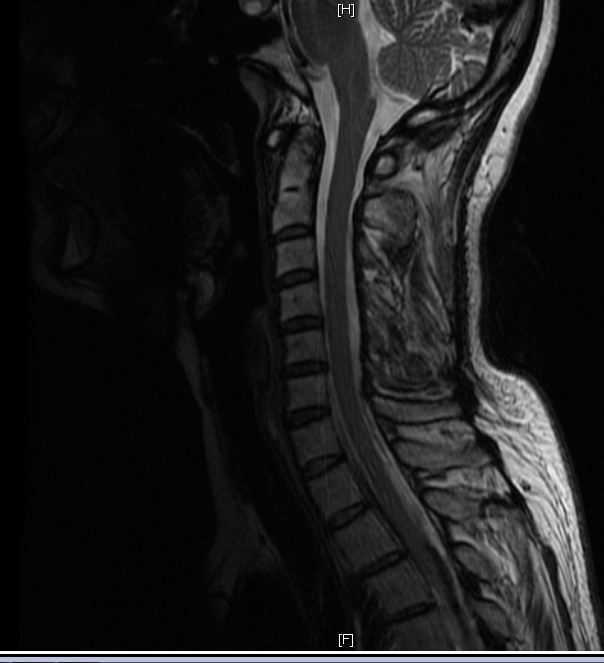

Ich lebe zur Zeit außerhalb Deutschlands und habe hier einen Orthopäden besucht und ein MRT der HWS machen lassen. Er diagnostizierte Muskelspasm rechte Seite (vom Schädelbasis bis ungefähr 5 cm nach unten). Der Orthopäde findet, dass der Dens nicht zentriert ist. Seiner Meinung nach haben das viele Leute, es sei normal.